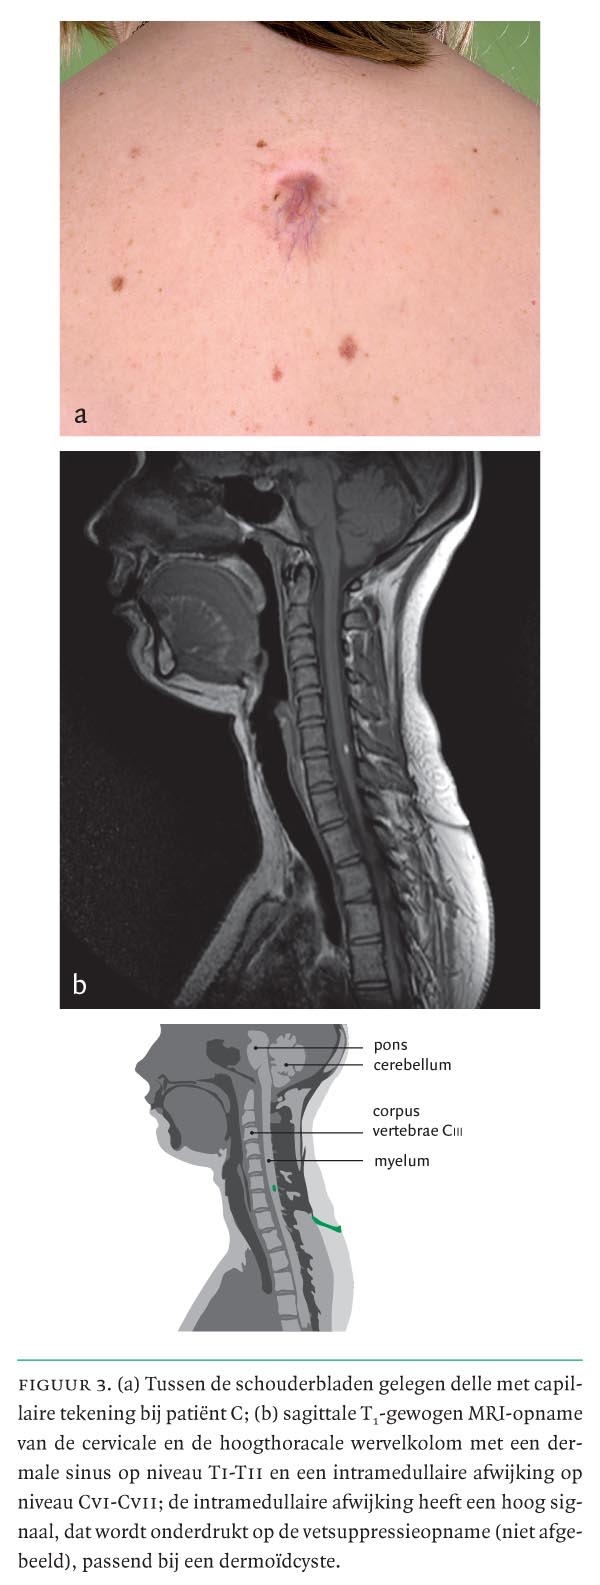

Het bekendste neurale sluitingsdefect is de spina bifida aperta, in de volksmond ‘open ruggetje’ genoemd. Daarnaast zijn er nog diverse andere verschijningsvormen van neurale sluitingsdefecten. Het grootste deel hiervan is niet duidelijk zichtbaar aan de buitenkant van het lichaam. Men spreekt dan van een occult sluitingsdefect. Een dergelijk sluitingsdefect wordt meestal niet als zodanig herkend. Bij de zogenaamde neurodermale sluitingsdefecten kan er een subtiele huidafwijking zichtbaar zijn, die kan duiden op een onderliggende afwijking. Deze afwijking kan gepaard gaan met een infectie of neurologische verschijnselen; daarom is onderkenning, controle en eventuele behandeling ervan noodzakelijk.

In deze les demonstreren wij u 3 casussen van patiënten met huidafwijkingen in de mediaanlijn als uiting van een occult neurodermaal sluitingsdefect.